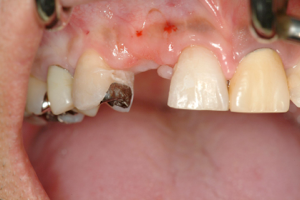

右の前歯が一本ありません。

最初の仮歯の状態です。

症例2

前歯の場合笑った時の歯の

見え方、歯茎の見え方も注意してインプラントの位置を考え

なければなりません。

他の残っているご自分の歯に

形を合わせないと審美的に

満足はえられません。